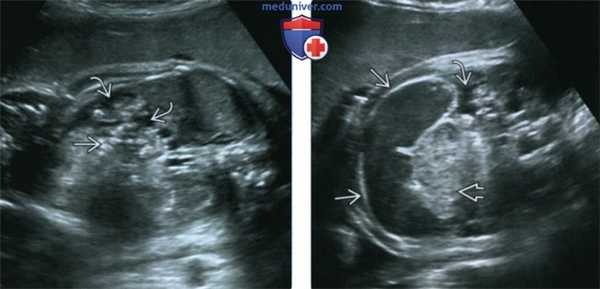

(Справа) Схожие фенотипические проявления у другого ребенка с СКДЛ. Особенно заметны тонкие «подведенные» брови и длинные ресницы. Отмечаются асимметричные тяжелые дефекты конечностей. (Слева) Плод с СКДЛ в III триместре. 3D УЗИ позволяет визуализировать фенотипические проявления синдромов, характеризующихся множественными аномалиями развития. Отчетливо визуализируются выступающее надпереносье, удлиненный губной желобок и микрогнатия. В конце III триместра могут также определяться удлиненные ресницы.

(Справа) Тот же новорожденный в профиль. Ушные раковины выглядят увеличенными за счет небольших размеров головки. Отмечаются удлиненный желобок и микрогнатия. (Слева) Фотография доношенного мертворожденного с СКДЛ и выраженной микрогнатией И Определяются довольно типичная монодакти-лия, один из вариантов редукционных дефектов конечности, а также мясистый вырост кожи.

(Справа) УЗИ верхней конечности плода во II триместре. СКДЛ. Обратите внимание на характерный дефект, монодактилию Пальцы и трубчатые кости дистального сегмента противоположной конечности отсутствуют. Подобная асимметрия дефектов конечностей крайне характерна для СКДЛ.